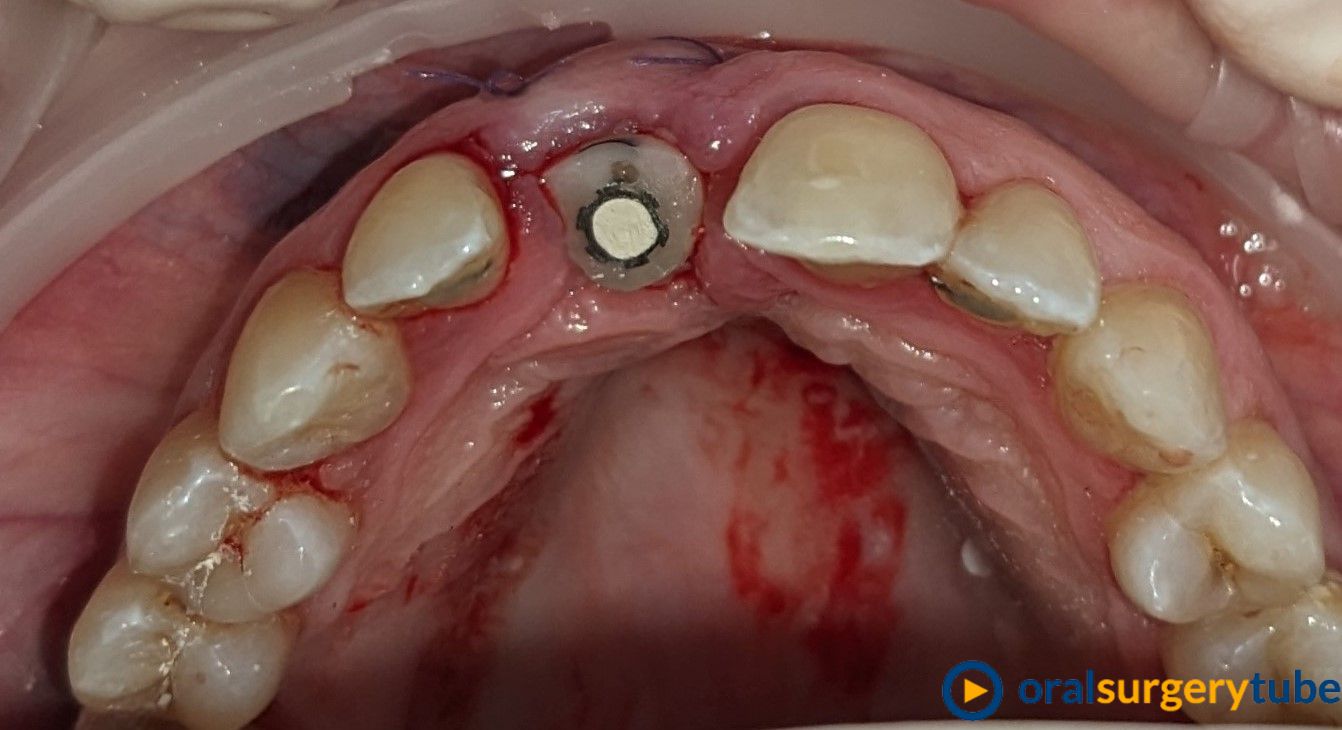

Paciente mujer joven, fumadora y de higiene regular. Con periodontitis moderada estabilizada pero con mal mantenimiento y con un proceso muy avanzado en el 21. Se le realiza en el mismo acto la extracción, legrado y lavado profuso, fresado y colocación guiada del implante con torque de 20N . Y después se regenera el aveolo con mix de autólogo de rama rascado con un micross y Bioss collagen y un injerto de tuberosidad en vestibular. No se hace carga inmediata por la baja estabilidad, se coloca y tapón de cicatrización y periacryl para sellar. Buscando un tratamiento similar (salvando mis infinitas limitaciones y distancias) a los protocolos de actuación de dos gigantes como Mesquita (implanteperio) y/o el de David González y su articulo de 3 Layers para alveolos sin tabla. Me decido por esta opción ya que todo lo que fuese levantar un colgajo sería al 100% un desastre estético y no estoy capacitado para un bloque mixto de tuberosidad ósea y blanda. Quizá haya fallado mi diagnostico o mi técnica.

Aparentemente la cicatrización es buena, asintomático y con buen aspecto. Pero en el control a 4 meses veo muchísima reabsorción de mi regeneración en vestíbulo. Sería por el potencial osteoclástico en ese lecho? o por no poner una capa de reabsorción lenta en la parte más externa?... en unos días probaré a ver si no me quedo con el implante en la mano.